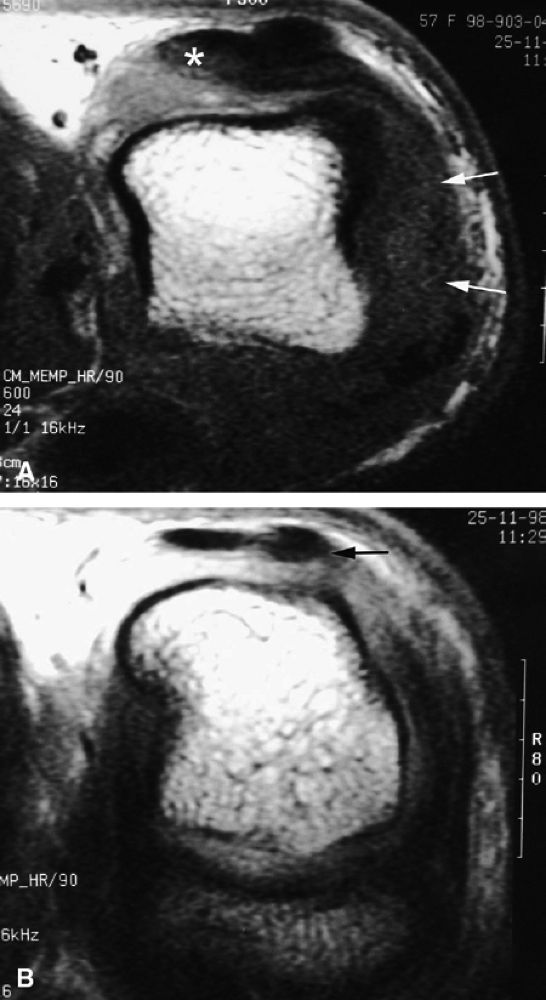

|

FIGURE 11.128 ● Vascular-type glomus tumor (asterisk) of the nail bed with the most common signal characteristics. (A) Axial T2-weighted image. T1-weighted images before (B) and after (C) injection of gadolinium. (D) MR angiogram. The tumor is located on the midline with an underlying bone erosion (arrowheads). The signal is high on T2-weighted images and slightly high on T1-weighted images. There is strong post-contrast enhancement on T1-weighted images and MR angiography.